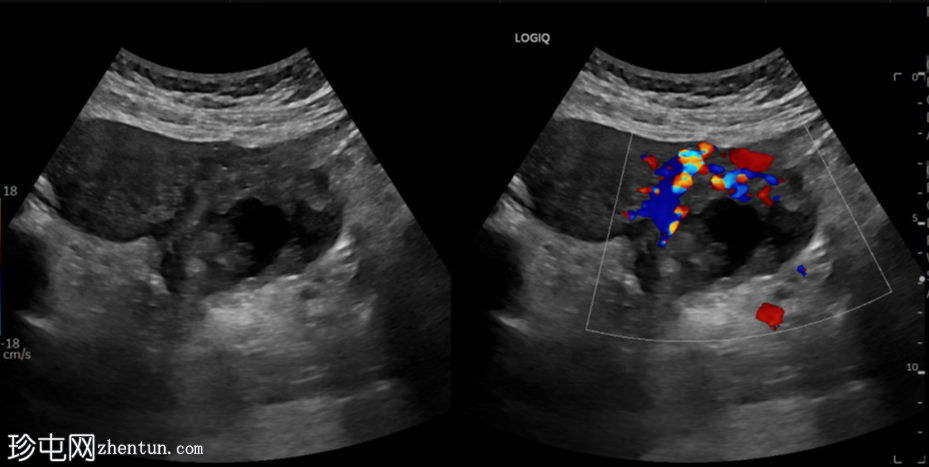

横切面

左侧卵巢明显增大,可见一囊肿,大小约3.2 x 2.3 cm,呈火环征,可能为黄体囊肿。左侧卵巢与子宫之间可见一管状结构,直径约1.3 cm,内含浑浊液体,未见血管,最可能为输卵管积血。以上特征提示可能为左侧异位妊娠。

未见宫内妊娠囊。